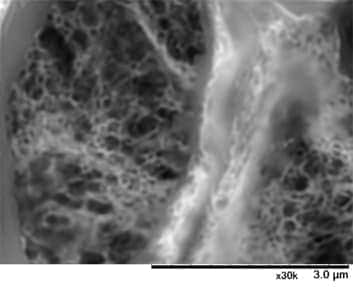

图示为Alport综合症患者的肾小球在低真空SEM下的图像(PAM染色)。

低真空SEM下清晰呈现基底膜的网状结构。